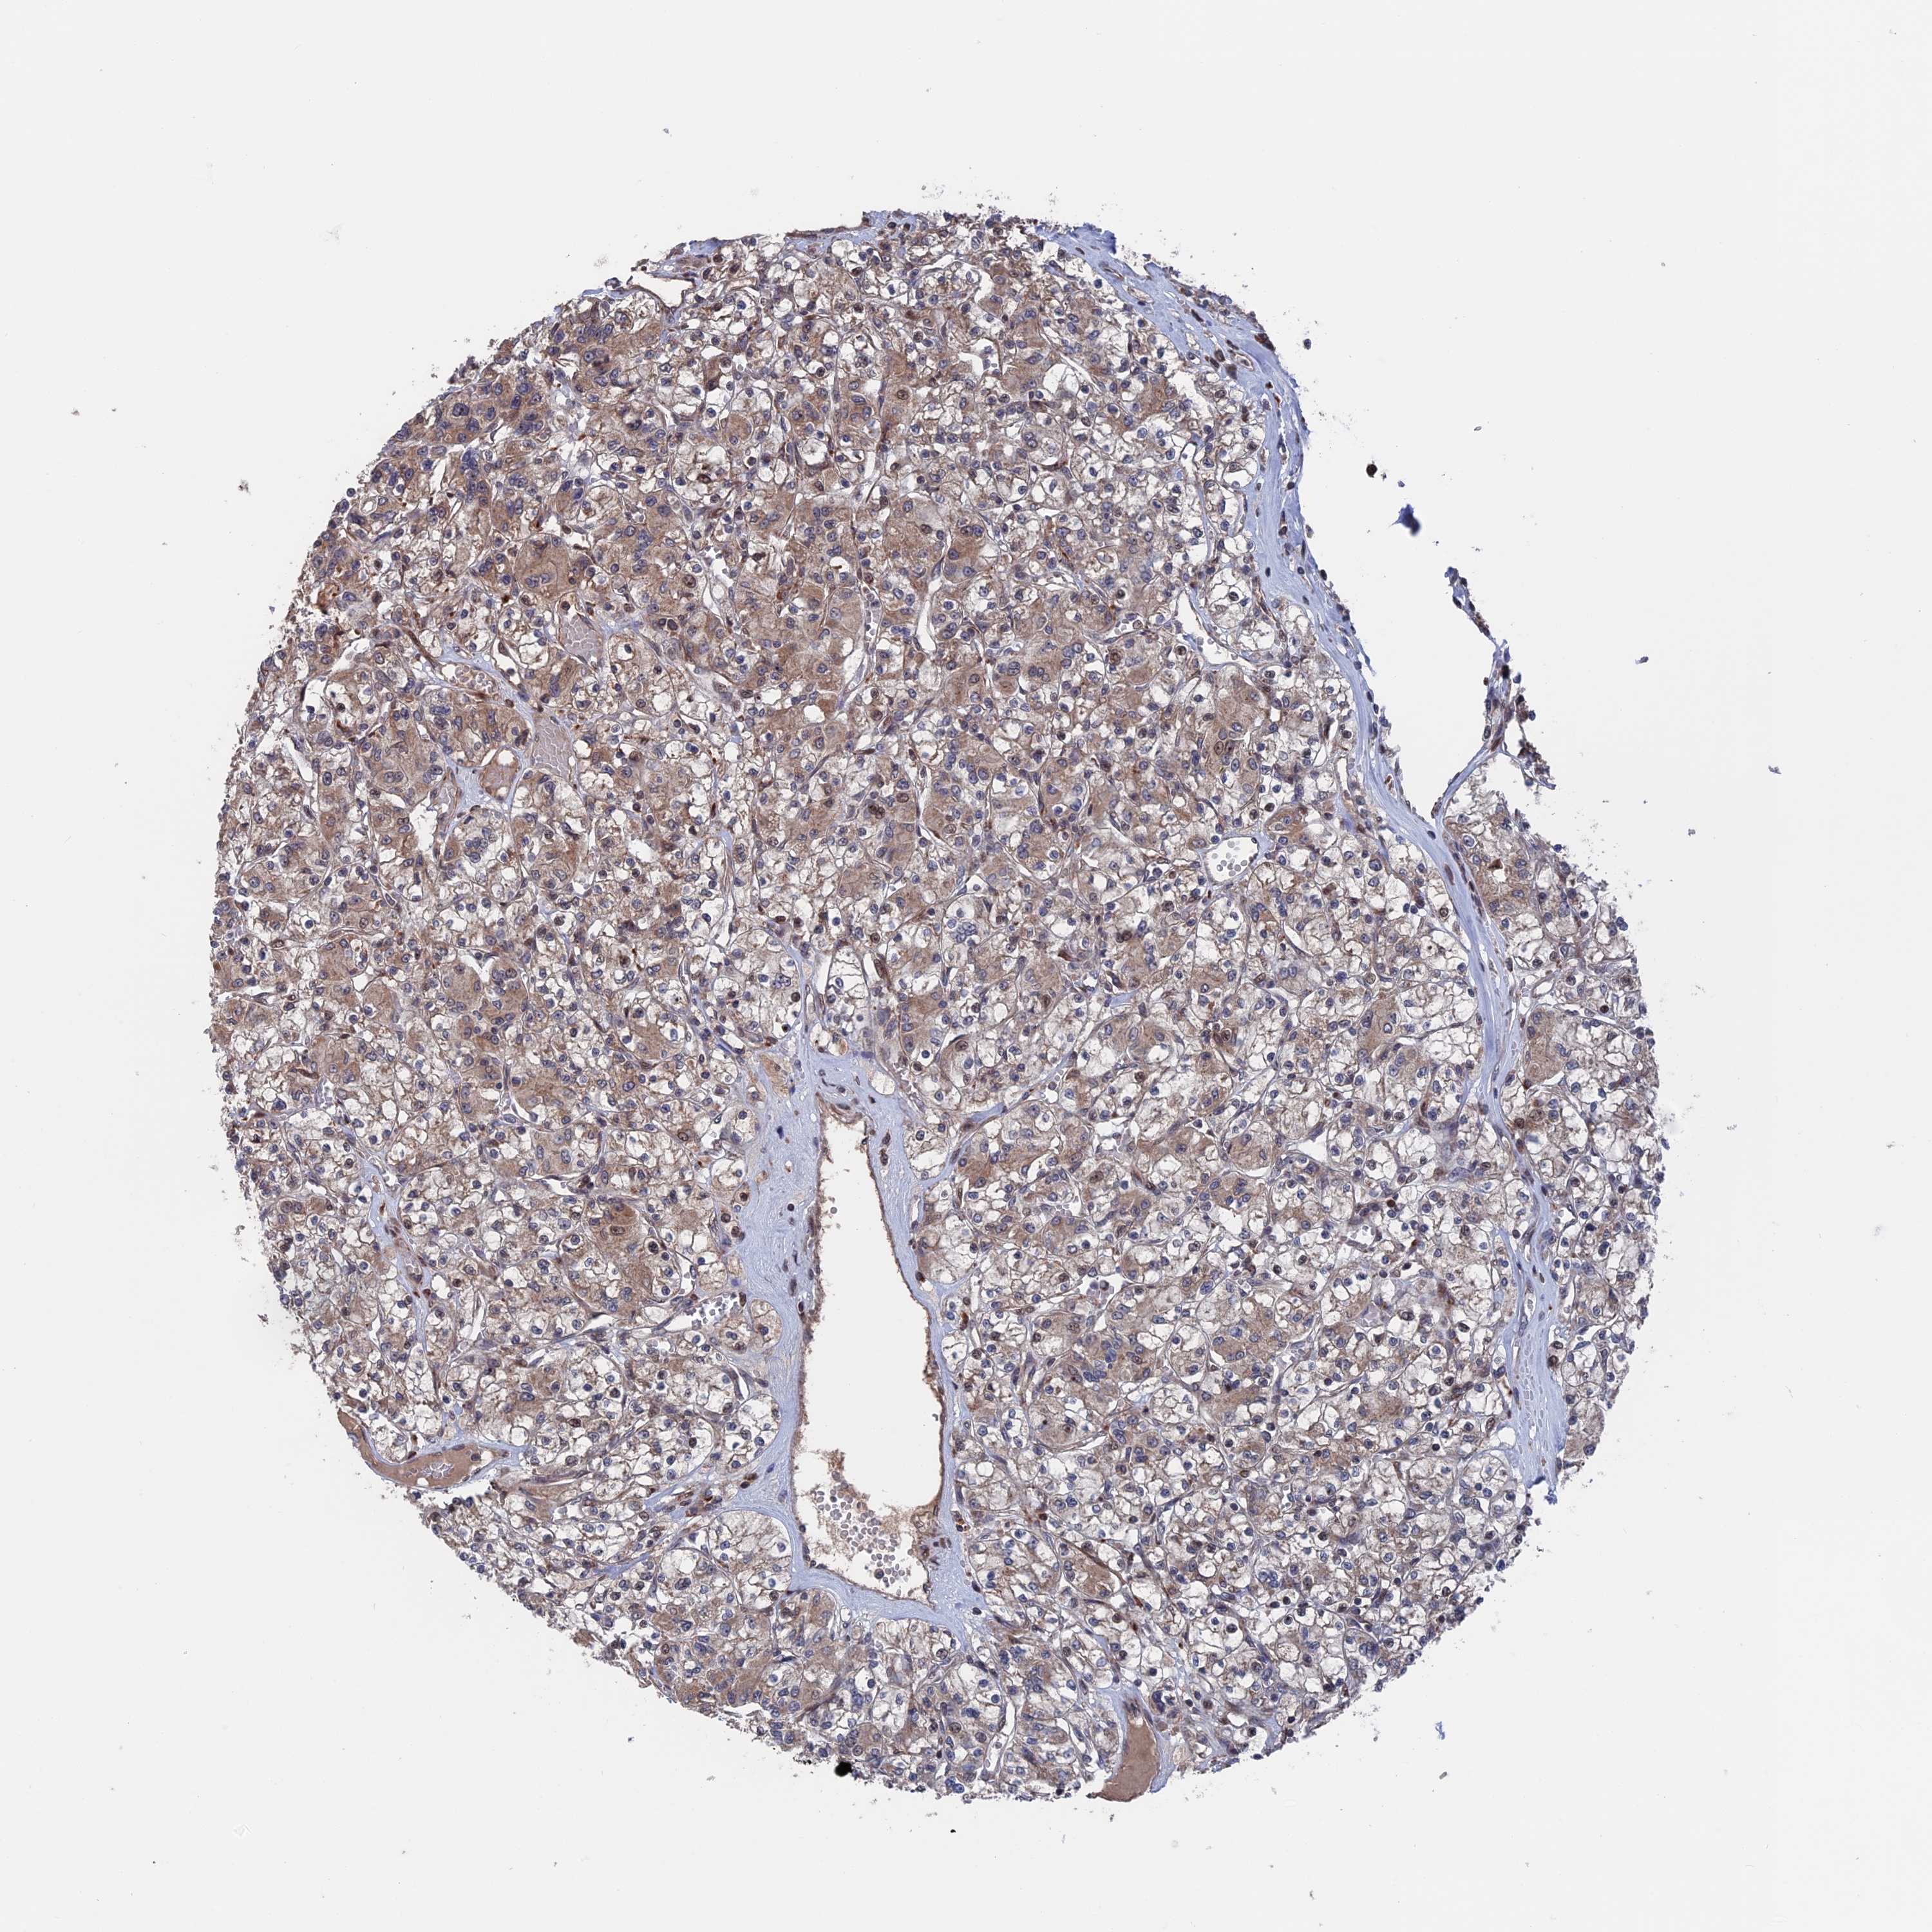

KIDNEY RENAL CLEAR CELL CARCINOMA (TCGA) - Interactive survival scatter ploti

The Survival Scatter plot shows the clinical status (i.e. dead or alive) for all individuals in the patient cohort, based on the same data that underlies the corresponding Kaplan-Meier plots. Patients that are alive at last time for follow-up are shown in blue and patients who have died during the study are shown in red.

The x-axis shows the expression levels (FPKM) of the investigated gene in the tumor tissue at the time of diagnosis. The y-axis shows the follow-up time after diagnosis (years). Both axes are complimented with kernel density curves demonstrating the data density over the axes. The top density plot shows the expression levels (FPKM) distribution among dead (red) and alive patients (blue). The right density plot shows the data density of the survived years of dead patients with high and low expression levels respectively, stratified using the cutoff indicated by the vertical dashed line through the Survival Scatter plot. This cutoff is automatically defined based on the FPKM cutoff that minimizes the p-score. The cutoff can be changed by dragging the vertical line or by entering a cutoff value in the square labeled "Current cut-off".

Under the Survival Scatter plot the p-score landscape (black curve; left axis) is shown together with dead median separation (red curve; right axis). Dead median separation is the difference in median mRNA expression between patients who have died with high and low expression, respectively. It is calculated as follows: median FPKM expression of dead patients with high expression - median FPKM expression of dead patients with low expression. This is intended to aid the user in visually exploring custom cutoffs and the associated p-scores and dead median separation.

Individual patient data is displayed and can be filtered by clicking on one or more of the category buttons on the top of the page. Categories describing expression level and patient information include: high, low, alive, dead, female, male and tumor stages. The scale of the x-axis can be toggled between linear and log-scale by clicking on the "x log" button. Mouse-over function shows TCGA ID, patient information and mRNA expression (FPKM) for each patient.

& Survival analysisi

Kaplan-Meier plots summarize results from analysis of correlation between mRNA expression level and patient survival. Patients were divided based on level of expression into one of the two groups "low" (under cut off) or "high" (over cut off). X-axis shows time for survival (years) and y-axis shows the probability of survival, where 1.0 corresponds to 100 percent.

PLA2G15 is not prognostic in Kidney Renal Clear Cell Carcinoma (TCGA)

Best expression cut offi

Based on the FPKM value of each gene, patients were classified into two groups and association between prognosis (survival) and gene expression (FPKM) was examined. The best expression cut-off refers the FPKM value that yields maximal difference with regard to survival between the two groups at the lowest log-rank P-value. Best expression cut-off was selected based on survival analysis .

When clicking on this number, the vertical dashed line indicating cut-off, the interactive survival plot, and the Kaplan-Meier curve will be adjusted to show results based on the best expression cut-off.

: 16.28

P scorei

Log-rank P value for Kaplan-Meier plot showing results from analysis of correlation between mRNA expression level and patient survival.

N/A

5-year survival highi

5-year survival for patients with higher expression than the expression cutoff.

For melanoma and glioma, 3-year survival is shown.

5-year survival lowi

5-year survival for patients with lower expression than the expression cutoff.

TCGA RNA samplesi

RNA-seq data is reported as average FPKM (number Fragments Per Kilobase of exon per Million reads), generated by the The Cancer Genome Atlas (TCGA) .

Normal distribution across the dataset is visualized with box plots, shown as median and 25th and 75th percentiles. Points are displayed as outliers if they are above or below 1.5 times the interquartile range. FPKM values of the individual samples are presented next to the box plot.

Average pTPM 23.1

Number of samples 521